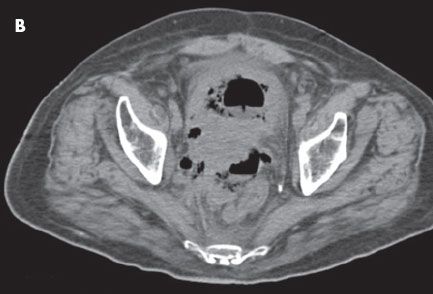

CT scans of the abdomen and pelvis showed a large prostatic mass without delineation between the prostate, rectum, and bladder. A fistula was noted between the rectum and bladder (A, B, and C). Copious subcutaneous gas was visible in the perineum and in all 3 corpora of the penis (D). Blood cultures were positive for Clostridium perfringens. Necrotizing fasciitis was diagnosed, and the patient underwent a loop colostomy.